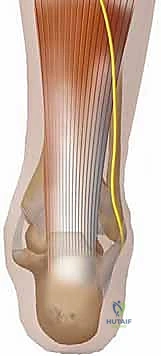

وتر أخيل ليس بنية مستقلة، بل هو الوتر النهائي المشترك الذي تتلاقى فيه ثلاث عضلات قوية تشكل ما يُعرف بـ "عضلات الساق ثلاثية الرؤوس" (Triceps Surae):

- العضلة التوأمية (Gastrocnemius): هي العضلة السطحية الكبيرة التي تعطي الساق شكلها المميز. تنشأ من اللقمتين الفخذيتين (الداخلية والخارجية) أعلى مفصل الركبة، مما يجعلها عضلة تعبر مفصلين (الركبة والكاحل). تساهم هذه العضلة بشكل رئيسي في الجزء السطحي والجانبي من وتر أخيل.

- العضلة النعلية (Soleus): عضلة قوية ومسطحة تقع بعمق تحت العضلة التوأمية. تنشأ من الجزء الخلفي لعظمي الساق (الظنبوب) والشظية. مساهمتها في وتر أخيل تكون عادة أكثر عمقاً وإنسيّة (نحو الداخل).

- العضلة الأخمصية (Plantaris): عضلة صغيرة ذات بطن عضلي قصير ووتر طويل جداً ورفيع، تسير جنباً إلى جنب مع وتر أخيل. رغم صغر حجمها، إلا أنها تُستخدم أحياناً كطعم جراحي لتعزيز إصلاح وتر أخيل المتمزق.

ظاهرة الدوران الداخلي (Tendon Rotation)

من أروع الظواهر التشريحية في وتر أخيل هي ظاهرة "الدوران". مع التقاء الألياف العضلية للعضلة التوأمية والنعلية ونزولها نحو الكعب، يخضع الوتر بأكمله لدوران داخلي مميز بزاوية تقارب 90 درجة. هذا الدوران ليس عشوائياً، بل هو تصميم هندسي رباني يزيد من مرونة الوتر وقدرته على تخزين وإطلاق الطاقة الحركية (مثل الزنبرك) وتقليل الضغط الميكانيكي المباشر على الألياف أثناء الحركة. نتيجة لهذا الدوران، تنتهي الألياف القادمة من العضلة النعلية (التي كانت عميقة) لتلتصق في الجزء الداخلي (الإنسي) من عظم الكعب، بينما تلتصق ألياف العضلة التوأمية في الجزء الخارجي (الوحشي).

نقطة الالتصاق والمحفظة الزلالية

يلتصق وتر أخيل بقوة في الثلث الأوسط من الحدبة الخلفية لعظم الكعب (Calcaneal Tuberosity). يوفر هذا الالتصاق العريض والقوي "ذراع رافعة" (Lever Arm) ميكانيكية هائلة، تُمكّن العضلات من سحب الكعب لأعلى، وبالتالي دفع القدم لأسفل (الثني الأخمصي - Plantarflexion).

على عكس العديد من الأوتار الأخرى في الجسم، لا يمتلك وتر أخيل غمداً زلالياً حقيقياً (Synovial Sheath)، بل يُحاط بطبقة رقيقة من الأنسجة الضامة تُسمى "الباراتينون" (Paratenon). هذه الطبقة غنية جداً بالأوعية الدموية وتلعب دوراً حاسماً في تغذية الوتر وانزلاقه بسلاسة، والحفاظ عليها أثناء الجراحة هو أحد أسرار نجاح تقنية الدكتور محمد هطيف.